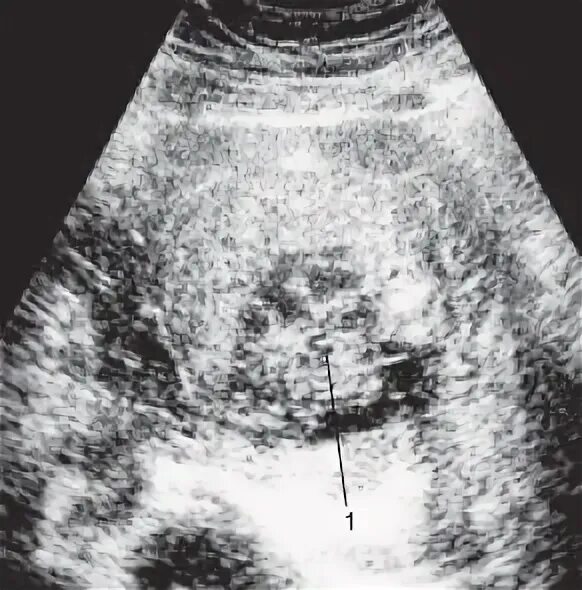

Мультикистозная почек плода